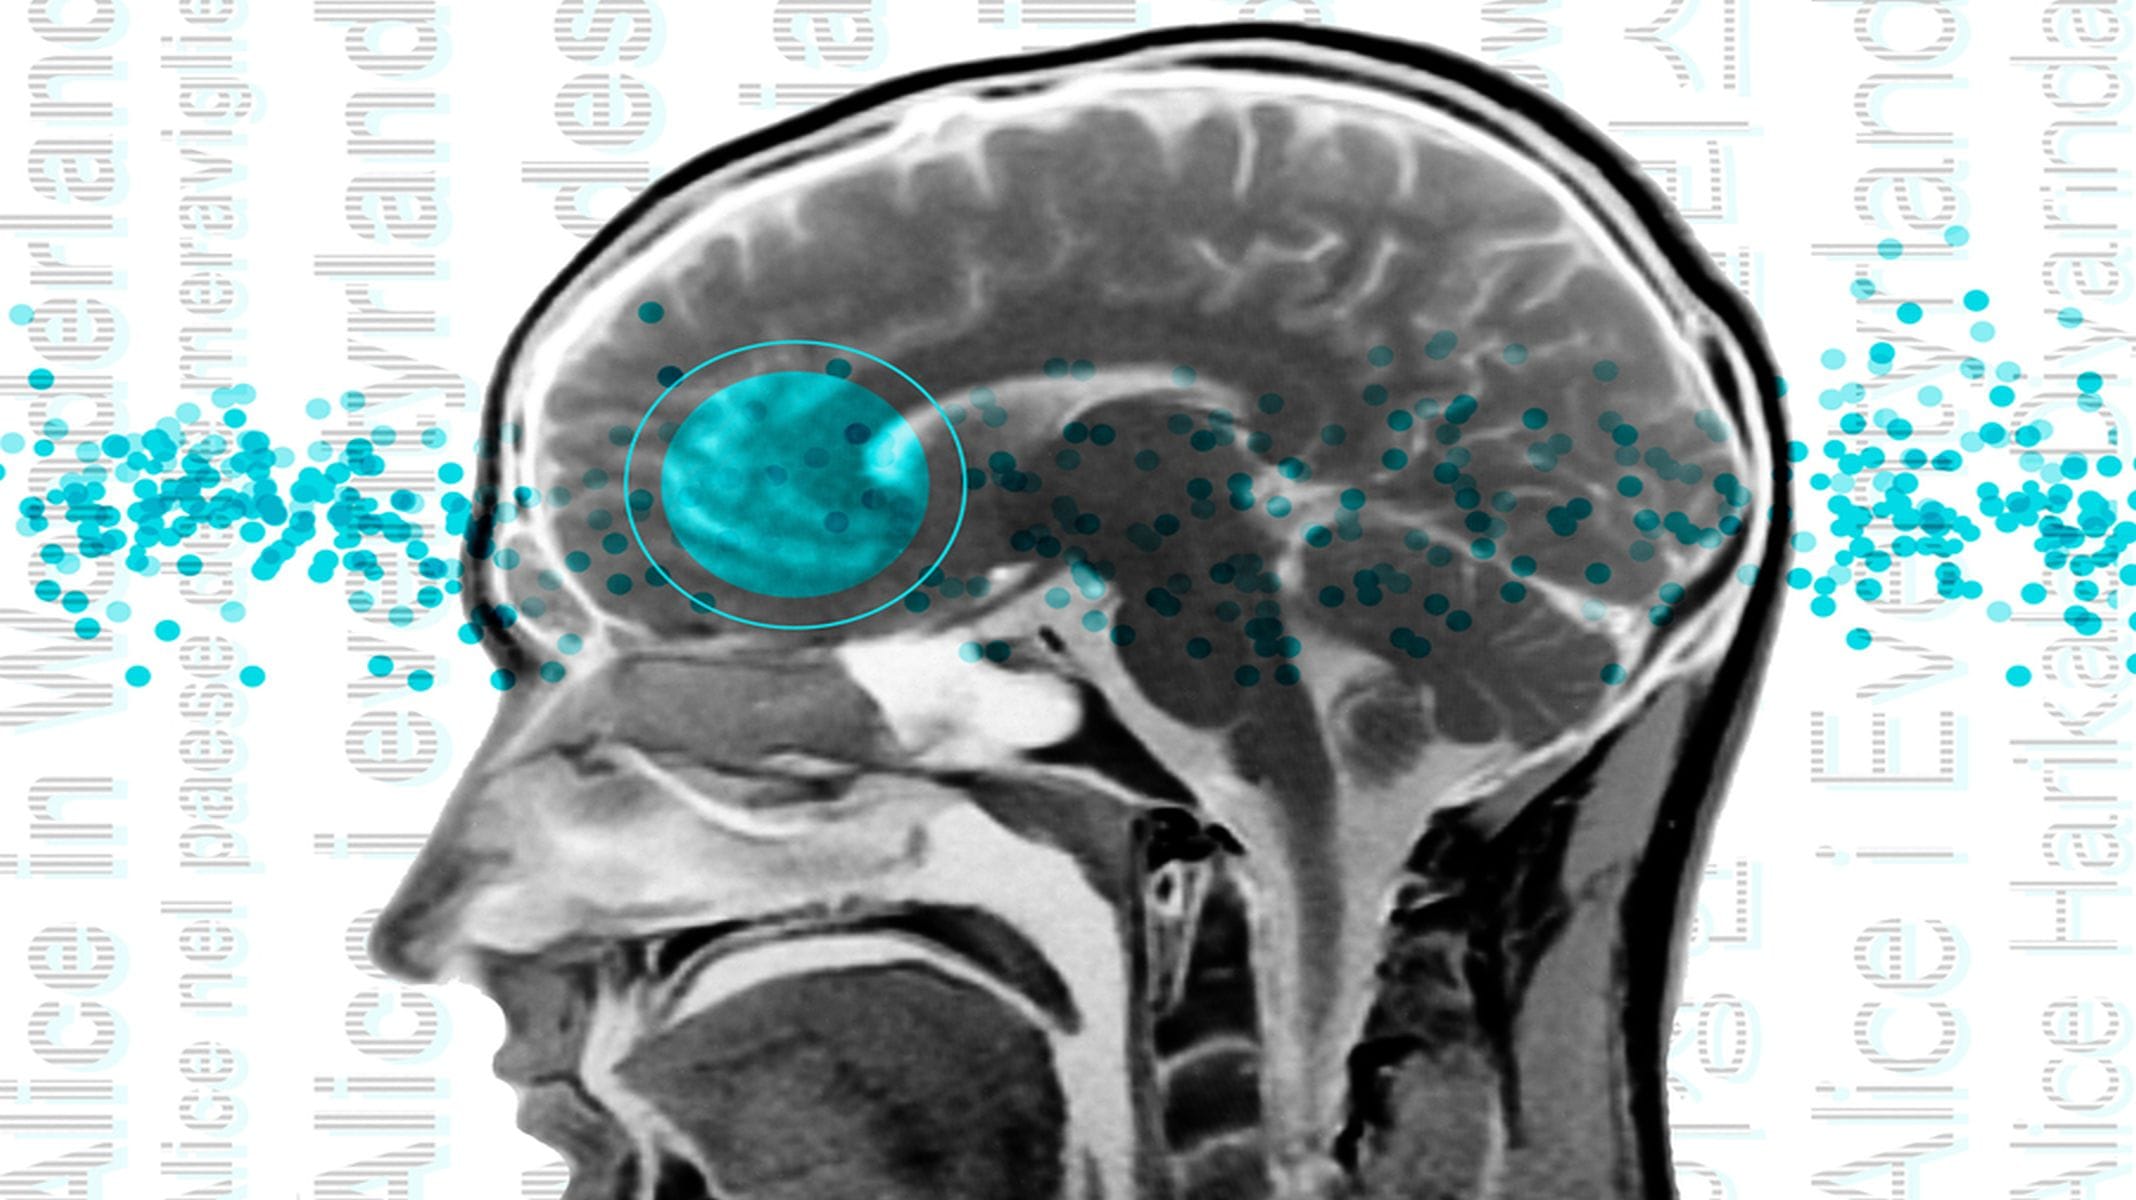

İnsan beyninin dili işlemek için kullandığı alanları, sinirbilimciler tarafından birkaç on yıl boyunca beynin “dil ağı” olarak haritalandı. Büyük ölçüde sol yarımkürede bulunan bu ağ, Broca bölgesindeki alanların yanı sıra diğer frontal ve temporal lob bölgelerinden oluşmaktadır.

Araştırmacılar, dil ağını tanımlamak için beyinlerini işlevsel manyetik rezonans görüntüleme ile tararken her kişinin bir dil mücadelesini tamamlamasını şart koşuyor. Çünkü her kişinin kendine özgü konumları ve dil alanlarının şekilleri farklılık gösteriyor (fMRI).

12 farklı dil grubunu kapsayan 45 farklı dilden iki konuşmacının beyinleri en son çalışma için görüntülendi. Katılımcıların dil ağlarının, ilk dili İngilizce olan bireylerle aynı konum, sol lobun çalışmasına ve seçiciliğe sahip olup olmadığını görmek istediler.

Araştırma ekibi, araştırmaya katılanların dil ağlarının yaklaşık olarak aynı beyin bölgelerinde bulunduğunu ve anadili İngilizce olanlarla aynı seçiciliğe sahip olduğunu keşfetti.